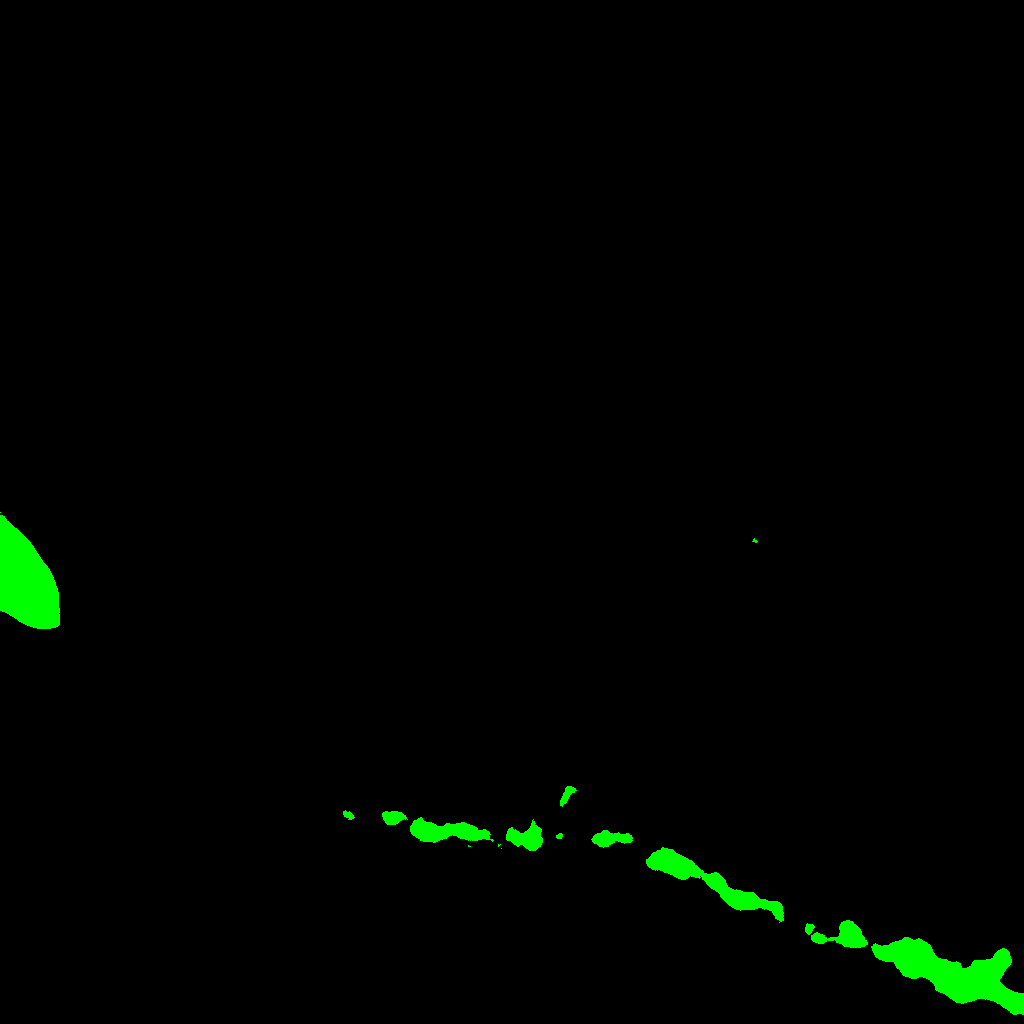

In order to construct a filtration of the binary image associated with the maximum projection image we proceed as follows. Dmsuperscript𝐷𝑚D^{m} is the maximum projection image. Dm1superscript𝐷𝑚1D^{m-1} consists of the connected components of Dmsuperscript𝐷𝑚D^{m} whose intersection with the first slide of the stack is non empty. Dm2superscript𝐷𝑚2D^{m-2} consists of the connected components of Dm1superscript𝐷𝑚1D^{m-1} whose intersection with the second slide of the stack is non empty, and so on. In general, Dmnsuperscript𝐷𝑚𝑛D^{m-n} consists of the connected components of Dmn+1superscript𝐷𝑚𝑛1D^{m-n+1} whose intersection with the n𝑛n-th slide of the stack is non empty. In this way, a filtration of the maximum projection image is obtained, see Figure 3.

Refer to caption\subseteqD0superscript𝐷0D^{0}Refer to caption\subseteqD1superscript𝐷1D^{1}Refer to caption\subseteqD2superscript𝐷2D^{2}Refer to caption\subseteqD3superscript𝐷3D^{3}Refer to caption\subseteqD4superscript𝐷4D^{4}Refer to caption\subseteqD5superscript𝐷5D^{5}Refer to caption\subseteqD6superscript𝐷6D^{6}Refer to caption\subseteqD7superscript𝐷7D^{7}Refer to captionD8superscript𝐷8D^{8}

Figure 3: A series of pictures depicting the process of filtration from the z-stack of Figure 1. From D0superscript𝐷0D^{0} to D8superscript𝐷8D^{8}: Starting on D0superscript𝐷0D^{0} and following to D8superscript𝐷8D^{8} each level of the filtration represent the containing, \subseteq information from the previous level. D8superscript𝐷8D^{8} contains all the connected components from the image.

As we know that the neuron appears in all the slides of the stack, the component D0superscript𝐷0D^{0} of our filtration will be the structure of the neuron. As a final remark, we can notice that the construction of the filtration reaches a point where it is stable; that is, a level of the filtration Disuperscript𝐷𝑖D^{i} of the filtration such that Djsuperscript𝐷𝑗D^{j} is equal to Disuperscript𝐷𝑖D^{i} for all 0j<i0𝑗𝑖0\leq j<i. An example can be seen in the components D0superscript𝐷0D^{0} to D4superscript𝐷4D^{4} of Figure 3. This observation will be important in the next subsection.